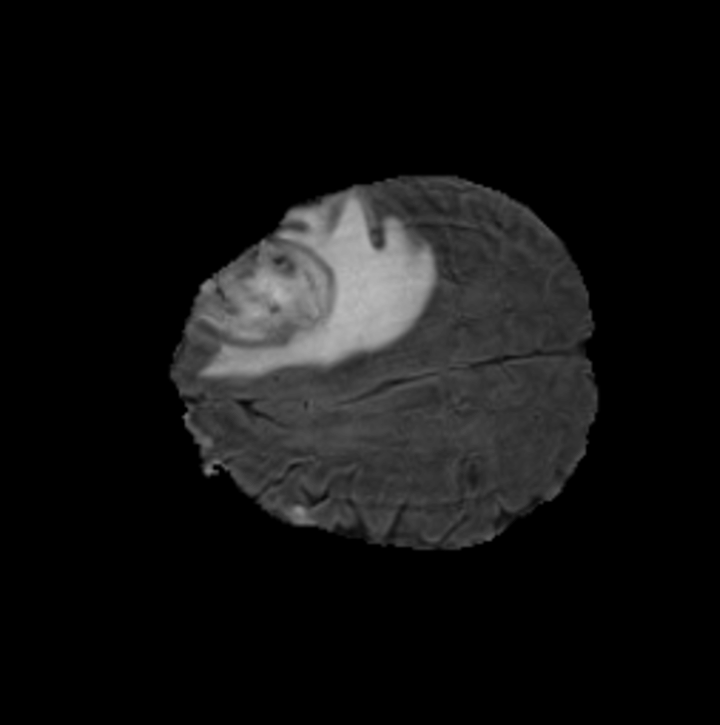

5.3 Out-of-Domain Generalisation

One way to test the generalization capability of the trained X-Diffusion is to test it on a completely different domain from an MRI dataset not seen during training. We report the single-slice results on NYU fastMRI [37, 82], a knee MRI dataset, using the X-Diffusion trained on the BRATS brain MRIs. The results are shown in Figure 9 and Table 2. It shows how successfully X-Diffusion is able to generate knee MRIs from a single image, despite not seeing knees at all in training. To qualitatively assess how realistic our generated 3D volumes were (produced from a single slice), we gave 20 generated examples alongside their real MRI counterparts to an expert orthopaedic surgeon. He was then asked to identify the real example from a given pair. The surgeon identified with certainty only 10 real knee MRIs out of 17, while could not decide on the remaining 3 of the 20 MRI pairs. This further validates the generated out-of-domain MRIs.